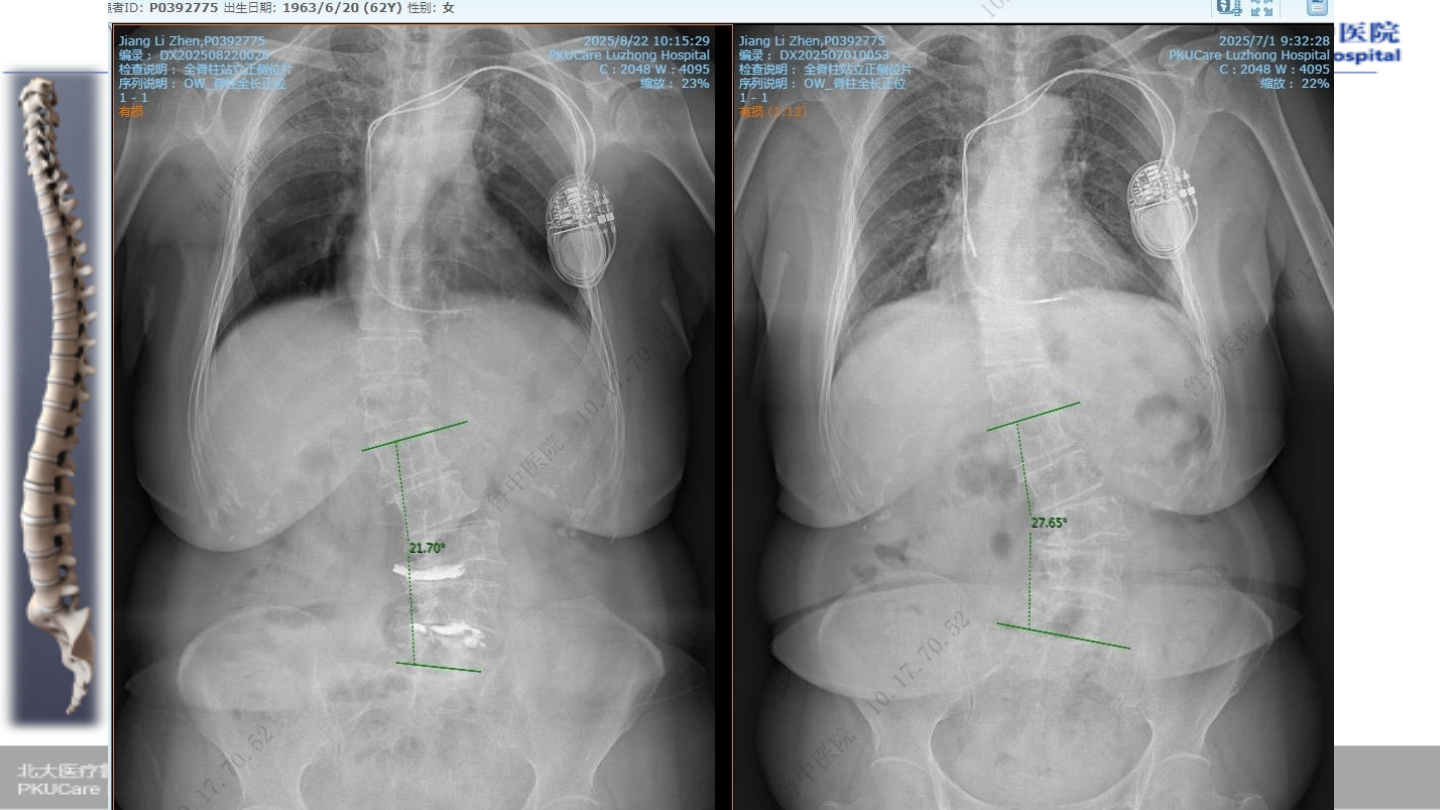

患者:姜某 女性,

67

主诉:

腰疼伴活动受限

2

症状:腰痛,活动后疼痛明显,跛行约

30

Oswestry

功能障碍指数(

ODI

):

85%

VAS

7

既往史:心脏起搏器植入史;焦虑症

病例

1

术前腰椎

x-ray